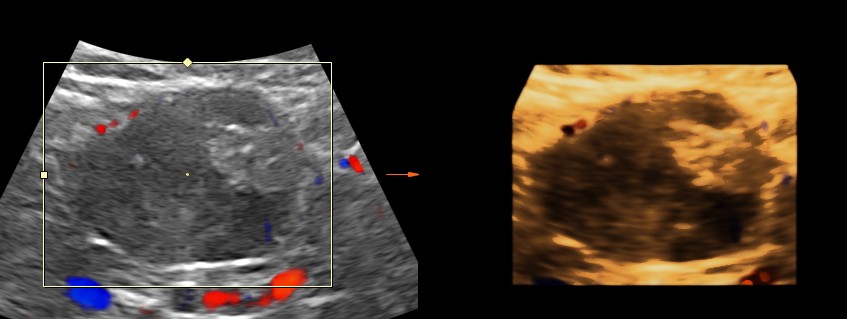

Now for the unexpected findings . To finish off the scan , I was sweeping the aorta, IVC and the pre and post aortic regions.

The following image was obtained with the transducer in the mid epigastric region and an inch to the left of the mid line.

This mass visualised there . This was antero-lateral to the aorta and showed mixed echotexture , with some vascularity.

This was not mobile and all i could offer was a description of what was seen with the impression of a mass of unknown origin – ?? enlarged node and advised further work up.

He underwent a contrast CT and was found to have a mass arising from the intestinal wall. He underwent surgery subsequently and the mass was removed . It was a benign leiomyoma arising from the jejunal wall and showed some erosions on the inner aspect ( cause for the anemia ) . Now came the pleasant surprise for everybody.His anemia improved and his headaches disappeared totally. The explanation offered was reactive thrombocytosis due to the anemia probably caused the hemicranial pain and when that was taken care of he was better.